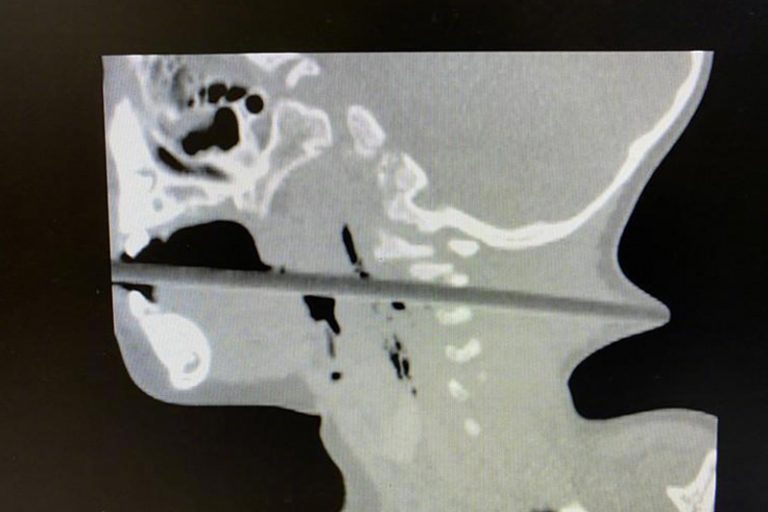

家人其後將林林送往南京市兒童醫院求診,該院神經外科主治醫師邱德智立即為林林安排做檢查。結果發現,長20多厘米的筷子從患者的「口腔進入,經過咽部後壁,通過頸椎2、3 間隙,一直向後到達後頸,幾乎戳穿了皮膚,從後頸可以清晰地看見筷頭。」